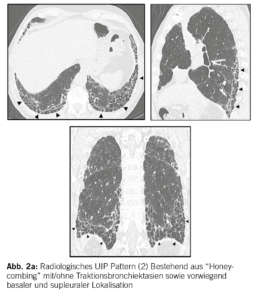

In der Bildgebung (HRCT (High resolution CT)) und/oder in den Biopsien finden wir dabei progrediente fibrotische Veränderungen. Insbesondere das Auftreten eines UIP-Pattern (usual interstitial pneumonia), siehe Abbildung 2a und 2b. geht mit einer Verschlechterung der Lungenfunktion und einer Zunahme der Morbidität und Mortalität einher.